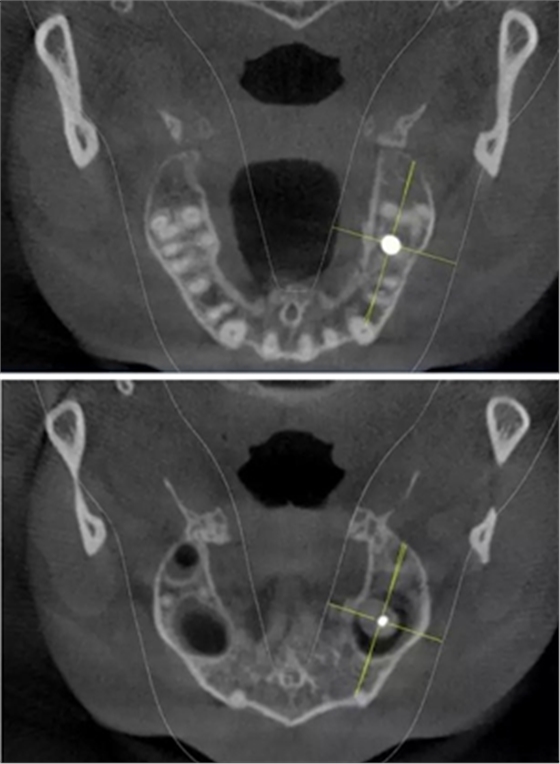

術(shù)前CBCT檢查

骨高度不足,內(nèi)提升的適應(yīng)癥??梢姼]膜致密,厚度均勻。骨高度不足,骨寬度尚可。

術(shù)后CBCT